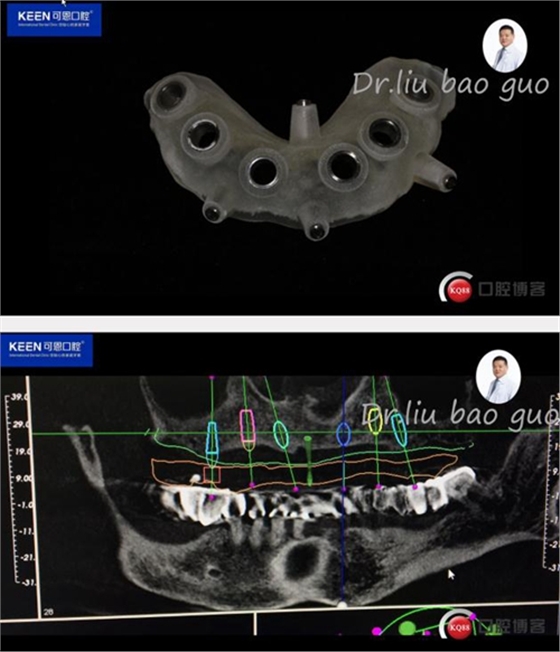

手術(shù)前種植軟件設(shè)計(jì)方案

數(shù)字化種植導(dǎo)板設(shè)計(jì)及制作